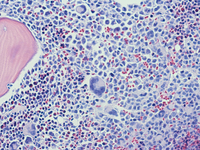

Small bowel biopsy

Small bowel resection shows an abnormal infiltration of discohesive cells with mucosal ulceration and granulation tissue. The cells are medium sized with occasional multinucleated giant cells. The background contains occasional eosinophils and neutrophils. By immunohistochemistry, the lesional cells show patchy weak CD45 staining and diffuse strong CD117 staining (shown here).